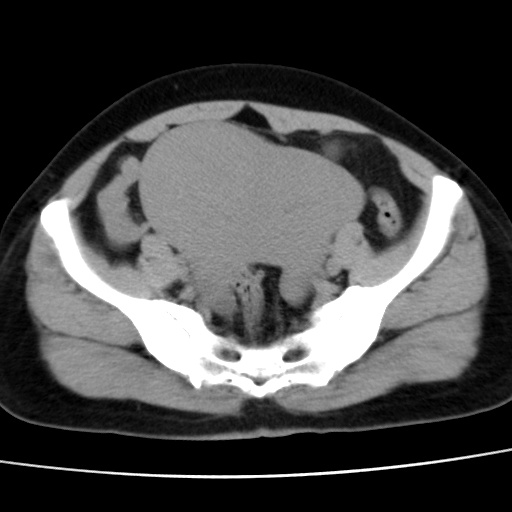

子宫多发肌瘤吗

多发性子宫肌瘤.

考虑多发子宫肌瘤,子宫直肠窝双囊性占位,另直肠周围脂肪密度增高,不知有何病史

支持考虑多发子宫肌瘤~!子宫直肠陷凹积液?

支持考虑多发子宫肌瘤~!子宫直肠陷凹积液!

子宫肌瘤,宫体部后方见液性密度影,是肠道还是子宫与直肠陷窝积液不好说,我觉得它的位置有点高

支持考虑多发子宫肌瘤!子宫直肠陷凹积液!

患者发热,而子宫直肠窝液性灶有明显边缘且局限且囊性,不除外为包裹性积液或脓肿

支持考虑多发子宫肌瘤,子宫直肠陷凹积液可能。

考虑多发子宫肌瘤

1)考虑子宫肌瘤可能性大。2)子宫后方囊性占位性病变,不排除卵巢囊肿可能。

考虑多发子宫肌瘤。子宫后方囊性占位性病变,不排除卵巢囊肿可能。